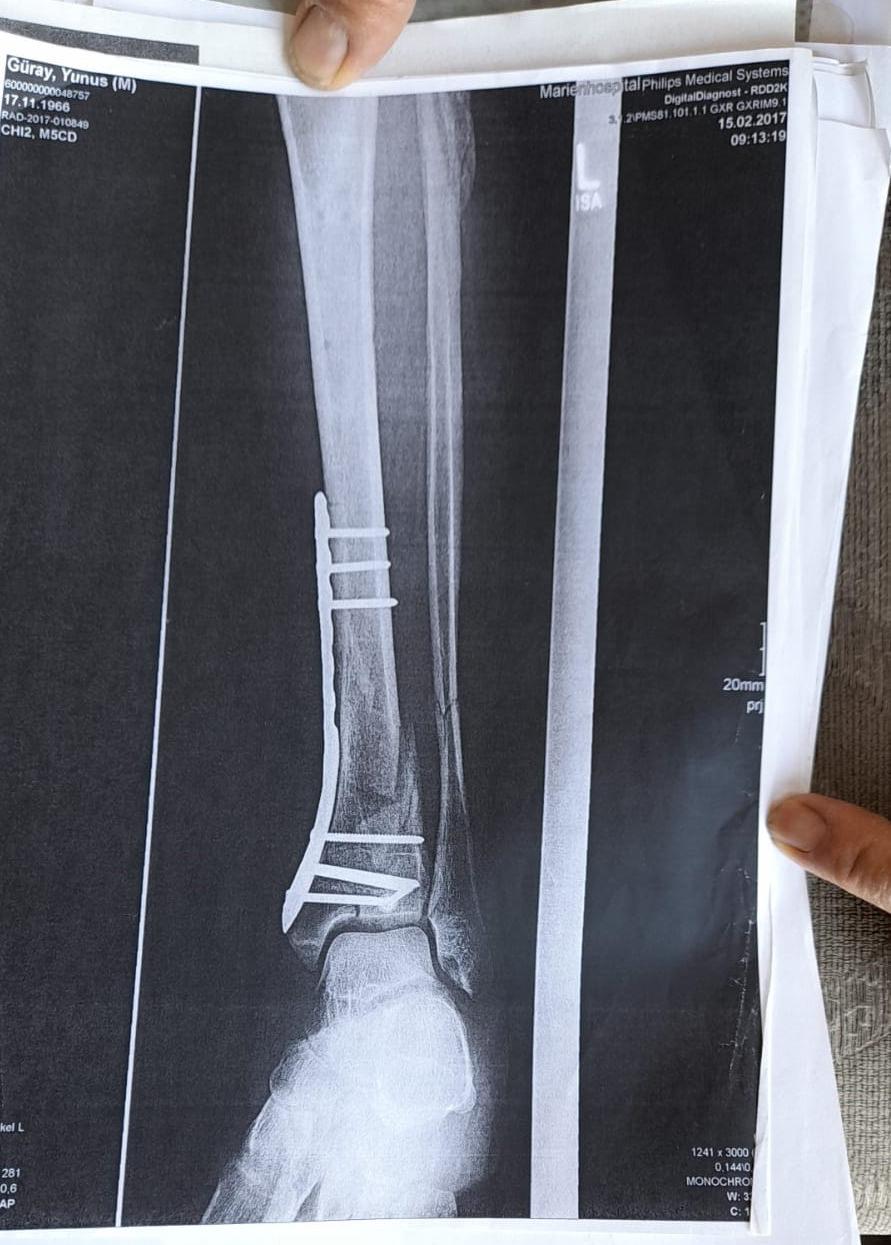

Olay yeriyle ilgili fotoğraf ve görüntüleri mahkemeye sunduklarını kaydeden Güray, "Ömrümü yediler, demir var ayağımda, sakat bıraktılar. Ayağı keseceklerdi neredeyse. Şu an kalıcı sakatlık var. 1 sene kendime gelemedim, 2 haftada bir ameliyata giriyordum. Almanya'da 3 ay hastanede kaldım ve ayağımda yüzde 3'lük engel oluştu." diye konuştu.